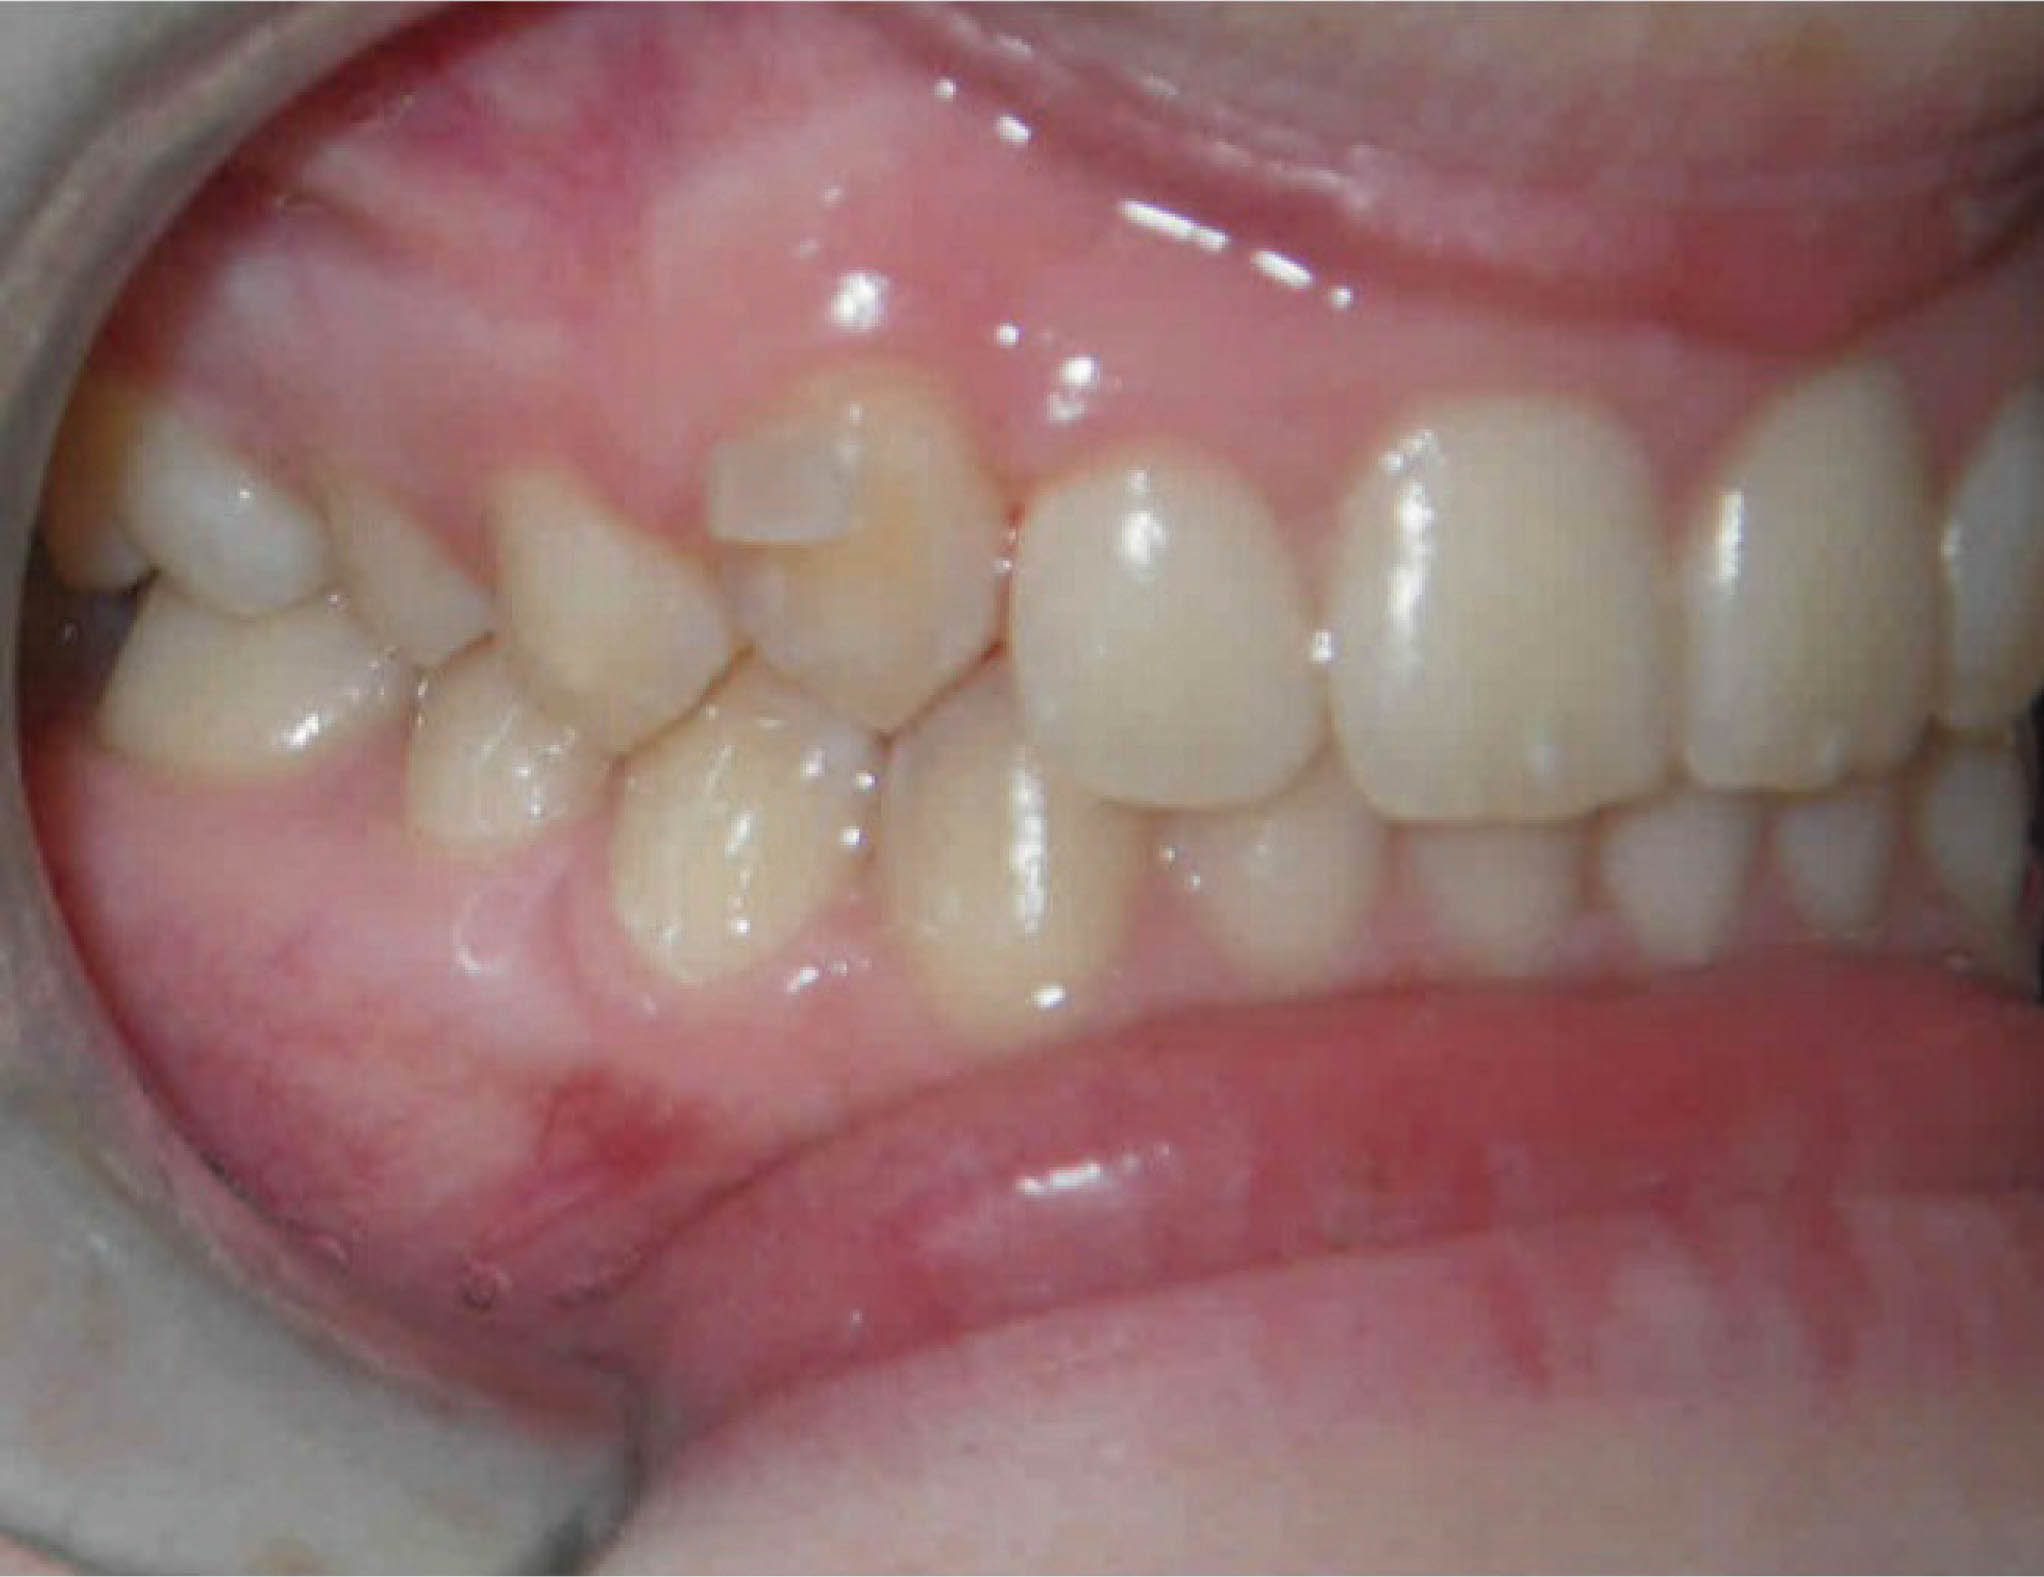

قانون کلی برای تورک ۳۰-۱۰ درجه درمان اضافه است که متناسب با بیمار شما تعیین میشود. در بیمار 167-6 باید لترالهای بالا را از کراس خارج کنیم. درمان چه با ارتو ثابت چه با الاینرها در سمت تاج رخ میدهد، لذا لترالها همیشه به سمت لبیال تیپ میشوند که میلی به این حالت نداریم. میخواهیم که این دندانها بادیلی حرکت کنند. برای این بیمار ۳۰ درجه حرکت بیشتر لبیالی ریشه لترالهای بالا در نظر گرفته شد.

شکل 167-6

تصویر 168-6 ماه ۲۲ را نشان میدهد، و میبینید که جایگاه لترال چپ بالا خوب است و ریشه هم وضعیت خوبی دارد. تورک اضافه باکالی ریشه ۳۰ درجه که به ریشه لترال بالا دادیم در دهان وجود ندارد. در واقع این میزان تورک برای جلوگیری از تیپ شدن لبیالی تاج و رسیدن به زاویه صحیح ریشه است.

شکل 168-6